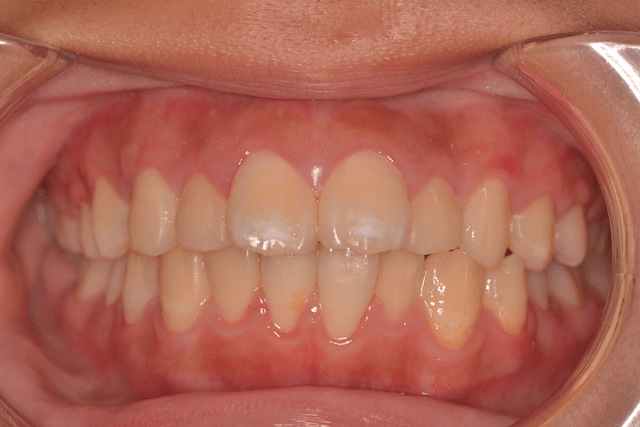

上顎前突(出っ歯)を抜歯とDBSで改善した症例

※DBSとはダイレクトボンディングシステムと呼ばれており、ブラケットにワイヤーを通して歯を動かしていく矯正治療です。

患者情報

16歳女性

主訴

口元下げたい

行った治療内容

上下顎両側4番抜歯、DBS

治療のリスク

歯根吸収、前歯部歯肉退縮

治療期間

動的治療期間2年9か月

※ クリックして拡大することができます。